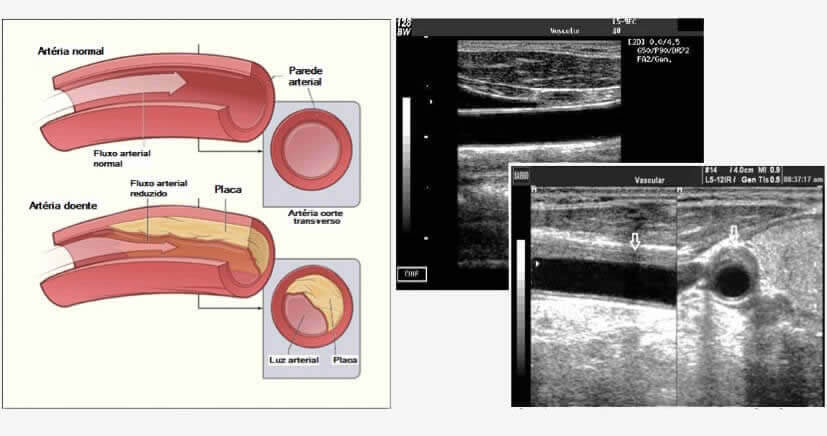

Aterosclerose

Aterosclerose é uma doença inflamatória crônica caracterizada pela formação de ateromas (placas) dentro dos vasos sanguíneos, na qual a placa pode acumular-se no trajeto das artérias. As artérias são vasos sanguíneos que transportam sangue rico em oxigênio do coração para outras partes do corpo. A placa é constituída por gordura, colesterol, cálcio e outras substâncias encontradas no sangue. Com o tempo, a placa endurece e reduz o calibre interno das artérias. Isso limita o fluxo de sangue arterial para os órgãos e outras partes do seu corpo. A aterosclerose pode levar a problemas graves, incluindo ataque cardíaco, acidente vascular cerebral, isquemia severa dos membros, podendo levar a morte.